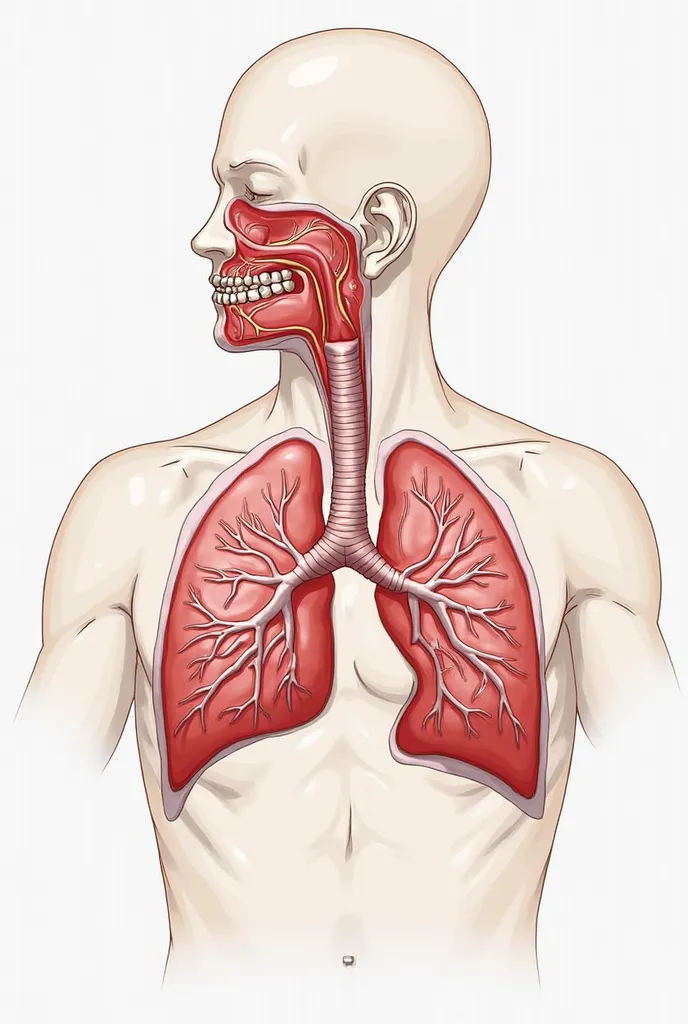

Pictures of swollen thyroid gland in neck, Use a Canon EOS 5D Mark IV with a 24

pictures of swollen thyroid gland in neck, Use a Canon EOS 5D Mark IV with a 24-70mm f/2.8 lens. Settings: ISO 100, aperture f/8, and shutter speed 1/125s to capture a sharp, vibrant image with a wide depth of field.

pictures of swollen thyroid gland in neck